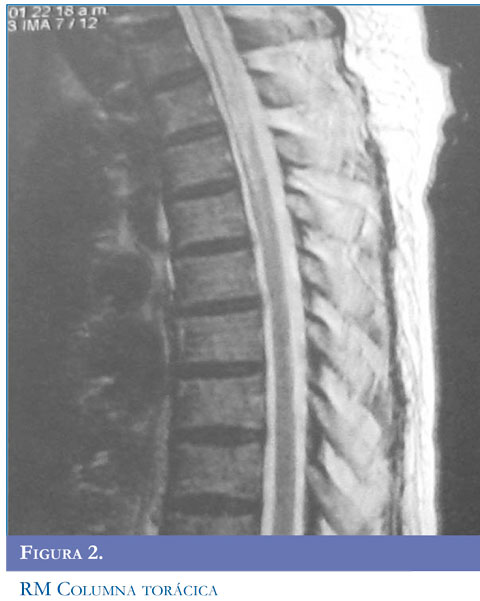

Hallazgos radiológicos

En la NMO, las lesiones de la médula espinal tienden a extenderse sobre tres o más segmentos vertebrales (Figuras 1 y 2 ). Se puede encontrar una apariencia de normalidad o menos lesiones, muy temprano en las recaídas o en la etapa atrófica residual (22). Las lesiones se observan como hiperinten-sidades en T2 e hipointensidades en T1 que suelen ocupar la mayor parte del área de sección transversal del segmento afectado y se asocian con inflamación y captación de gadolinio (23).